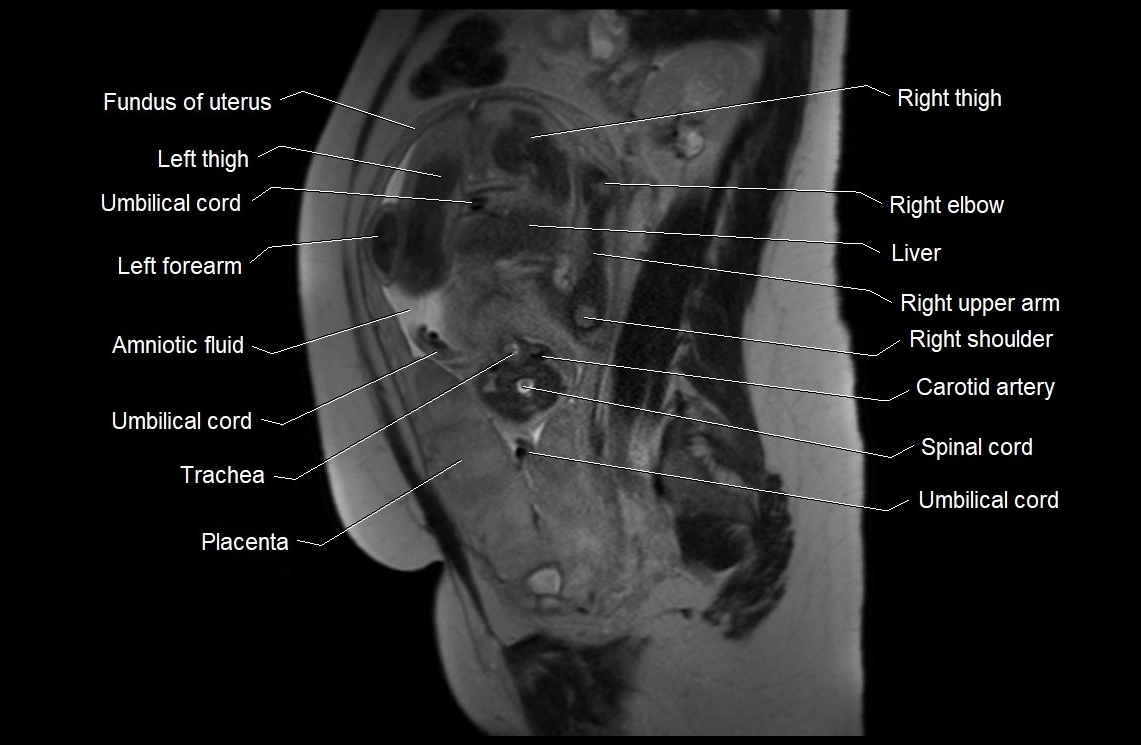

MRI Appearance

T2 HASTE (T2 GRE):

• Amniotic fluid shows very bright hyperintense signal

• Provides natural contrast against fetus and placenta

• Small particles (vernix) may appear as scattered hypointense foci within bright fluid

T1 GRE:

• Amniotic fluid shows low signal intensity (dark)

• Hemorrhage, infection, or proteinaceous content may cause focal or diffuse high signal intensity

MRI image

image